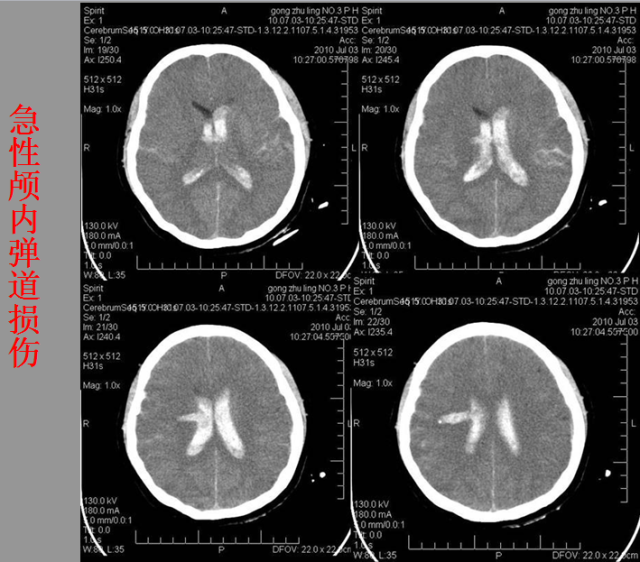

急性颅脑损伤篇

03